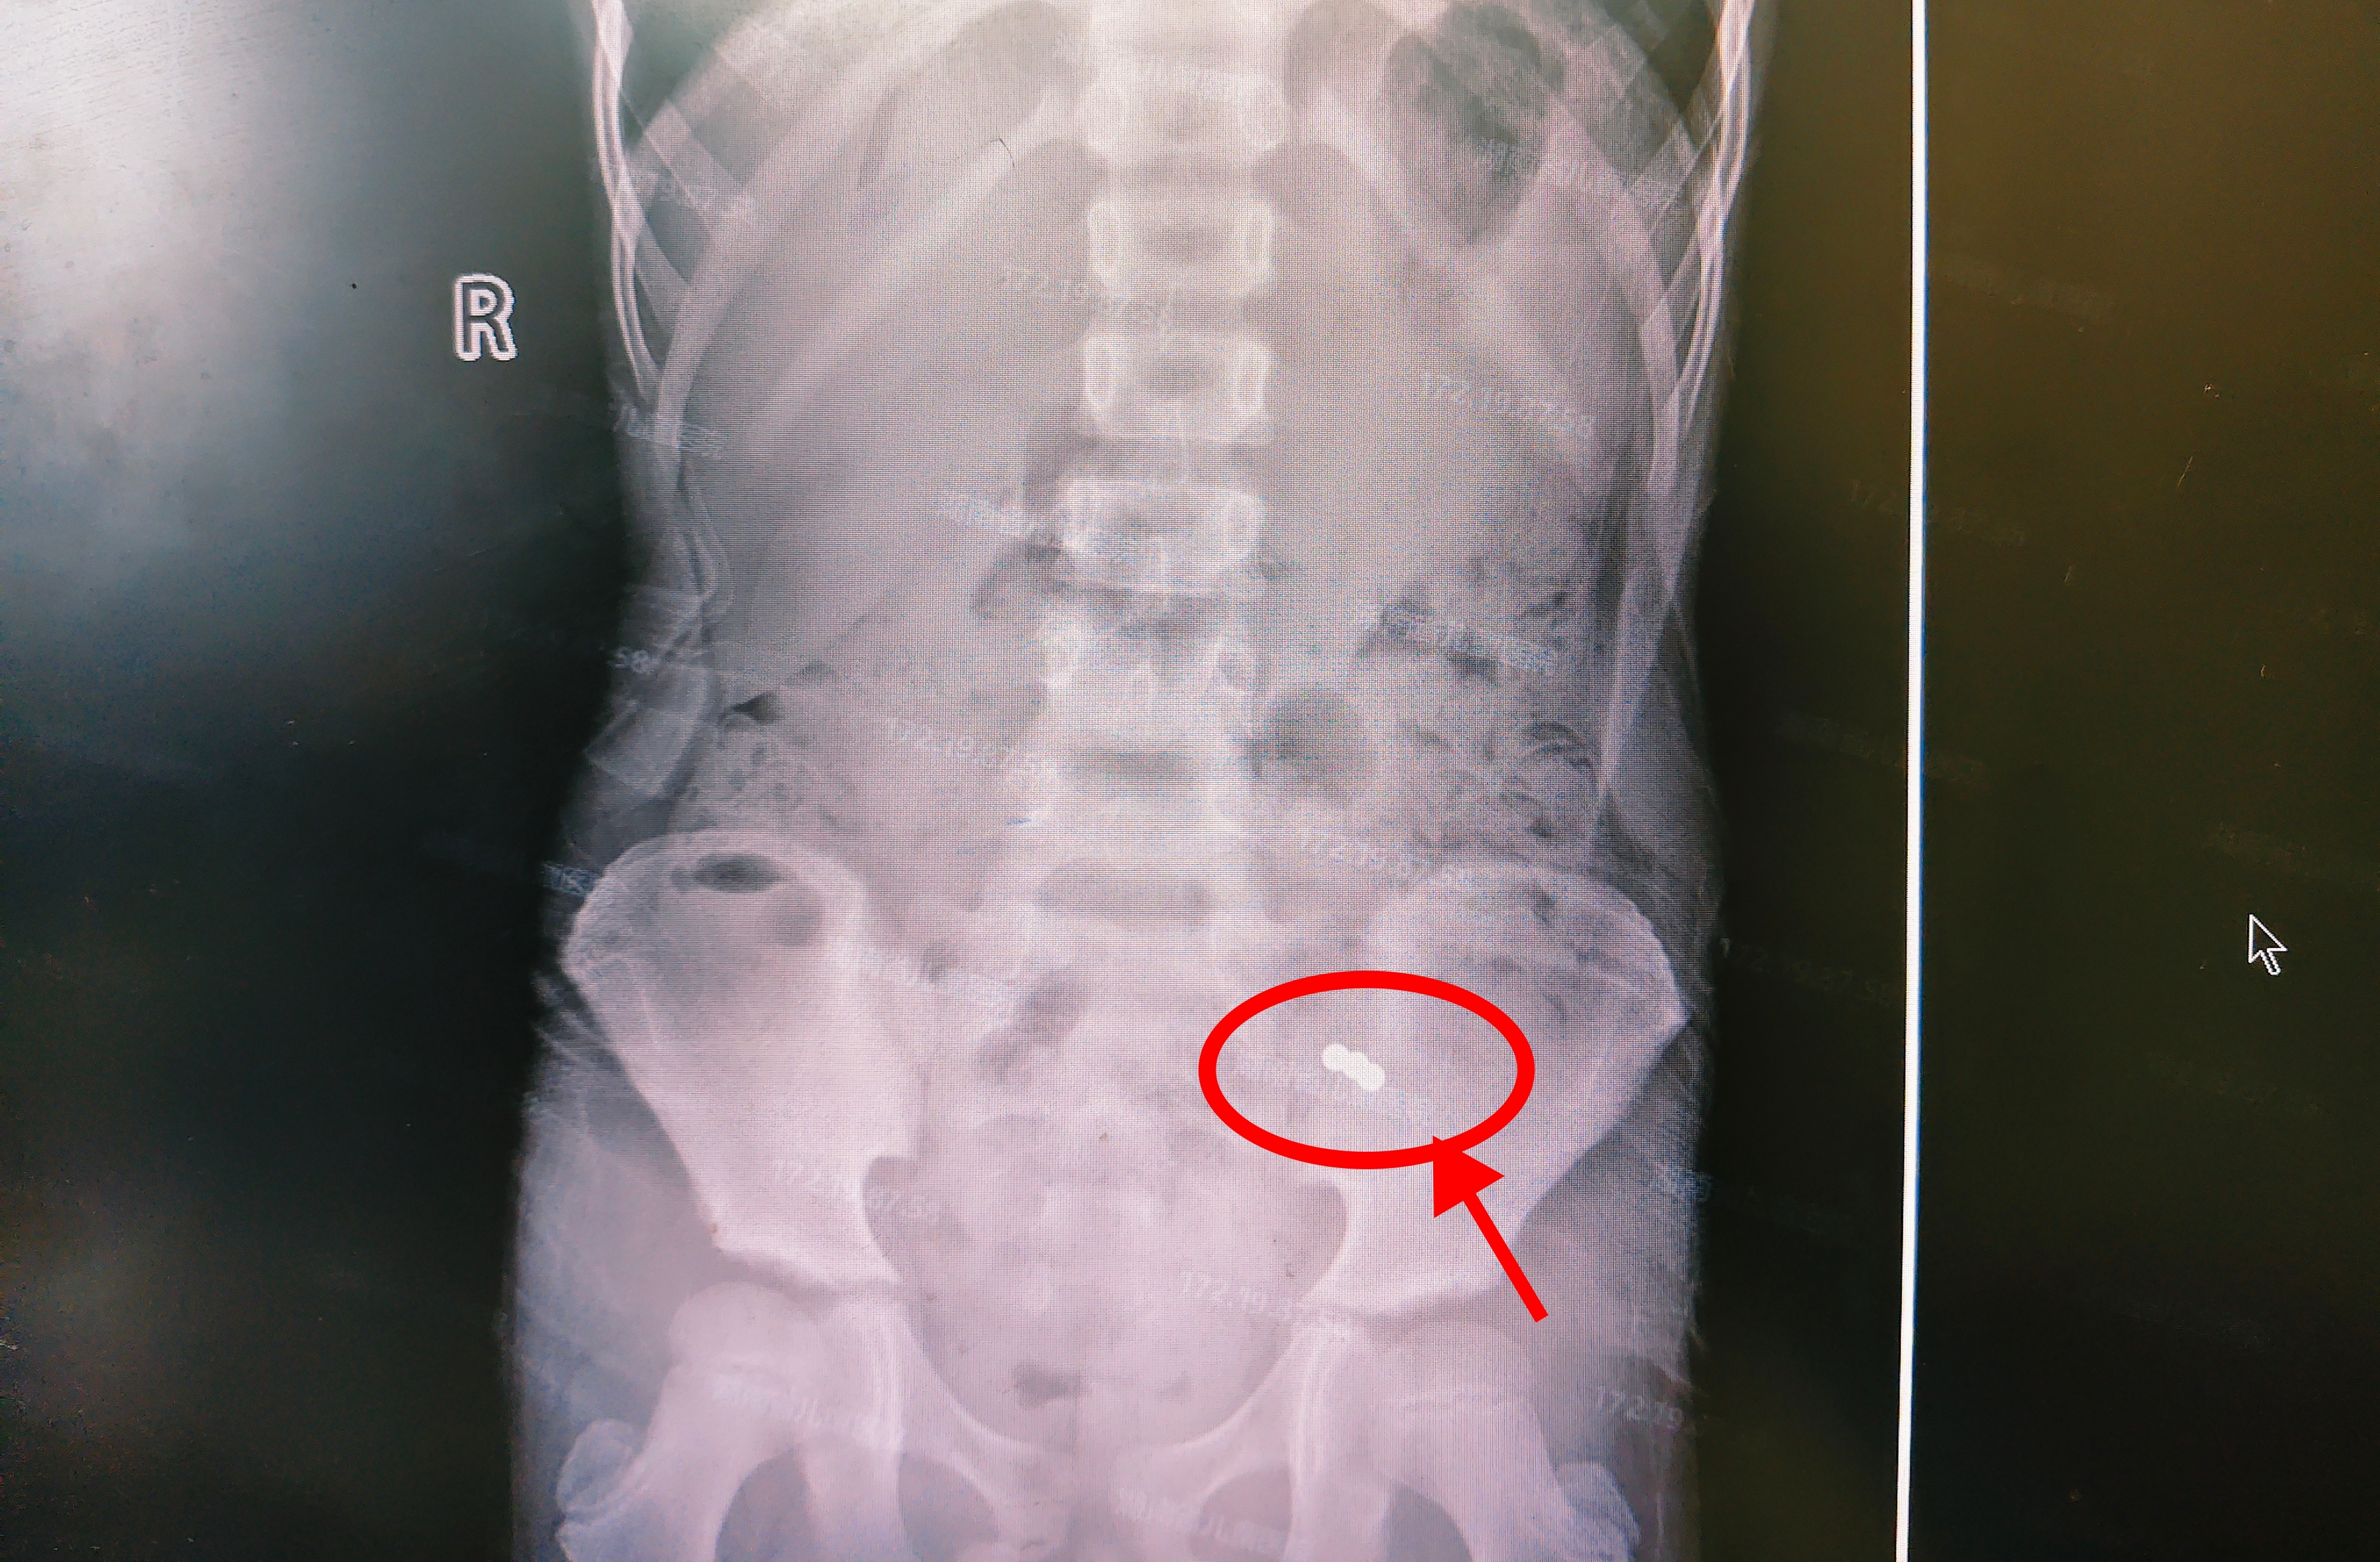

4月7日,潇湘晨报晨视频记者从湖南省儿童医院了解到,近日,9岁男童明明(化名)误吞了3粒磁珠,出现了反复腹痛的症状,家属为进一步治疗,带着明明来到了该院普外一科就诊。

医护团队完善了相关检查后,向其父母详细讲解了病情:由于误吞的磁珠长时间位置无变化,异物通过肠道蠕动功能自行排出的可能性小;若磁珠长期滞留在肠道内互相吸引,可能导致肠梗阻、肠管坏死穿孔,甚至诱发严重感染,产生不良后果。

经普外一科团队的精准评估,最终确定手术治疗为最佳治疗方案。在完成充分的术前准备后,手术团队为明明实施了急诊手术。术中医生发现,明明的肠管已有2处穿孔,凭借娴熟的技术,团队顺利在结肠穿孔处取出了3粒长约3mm的磁珠。